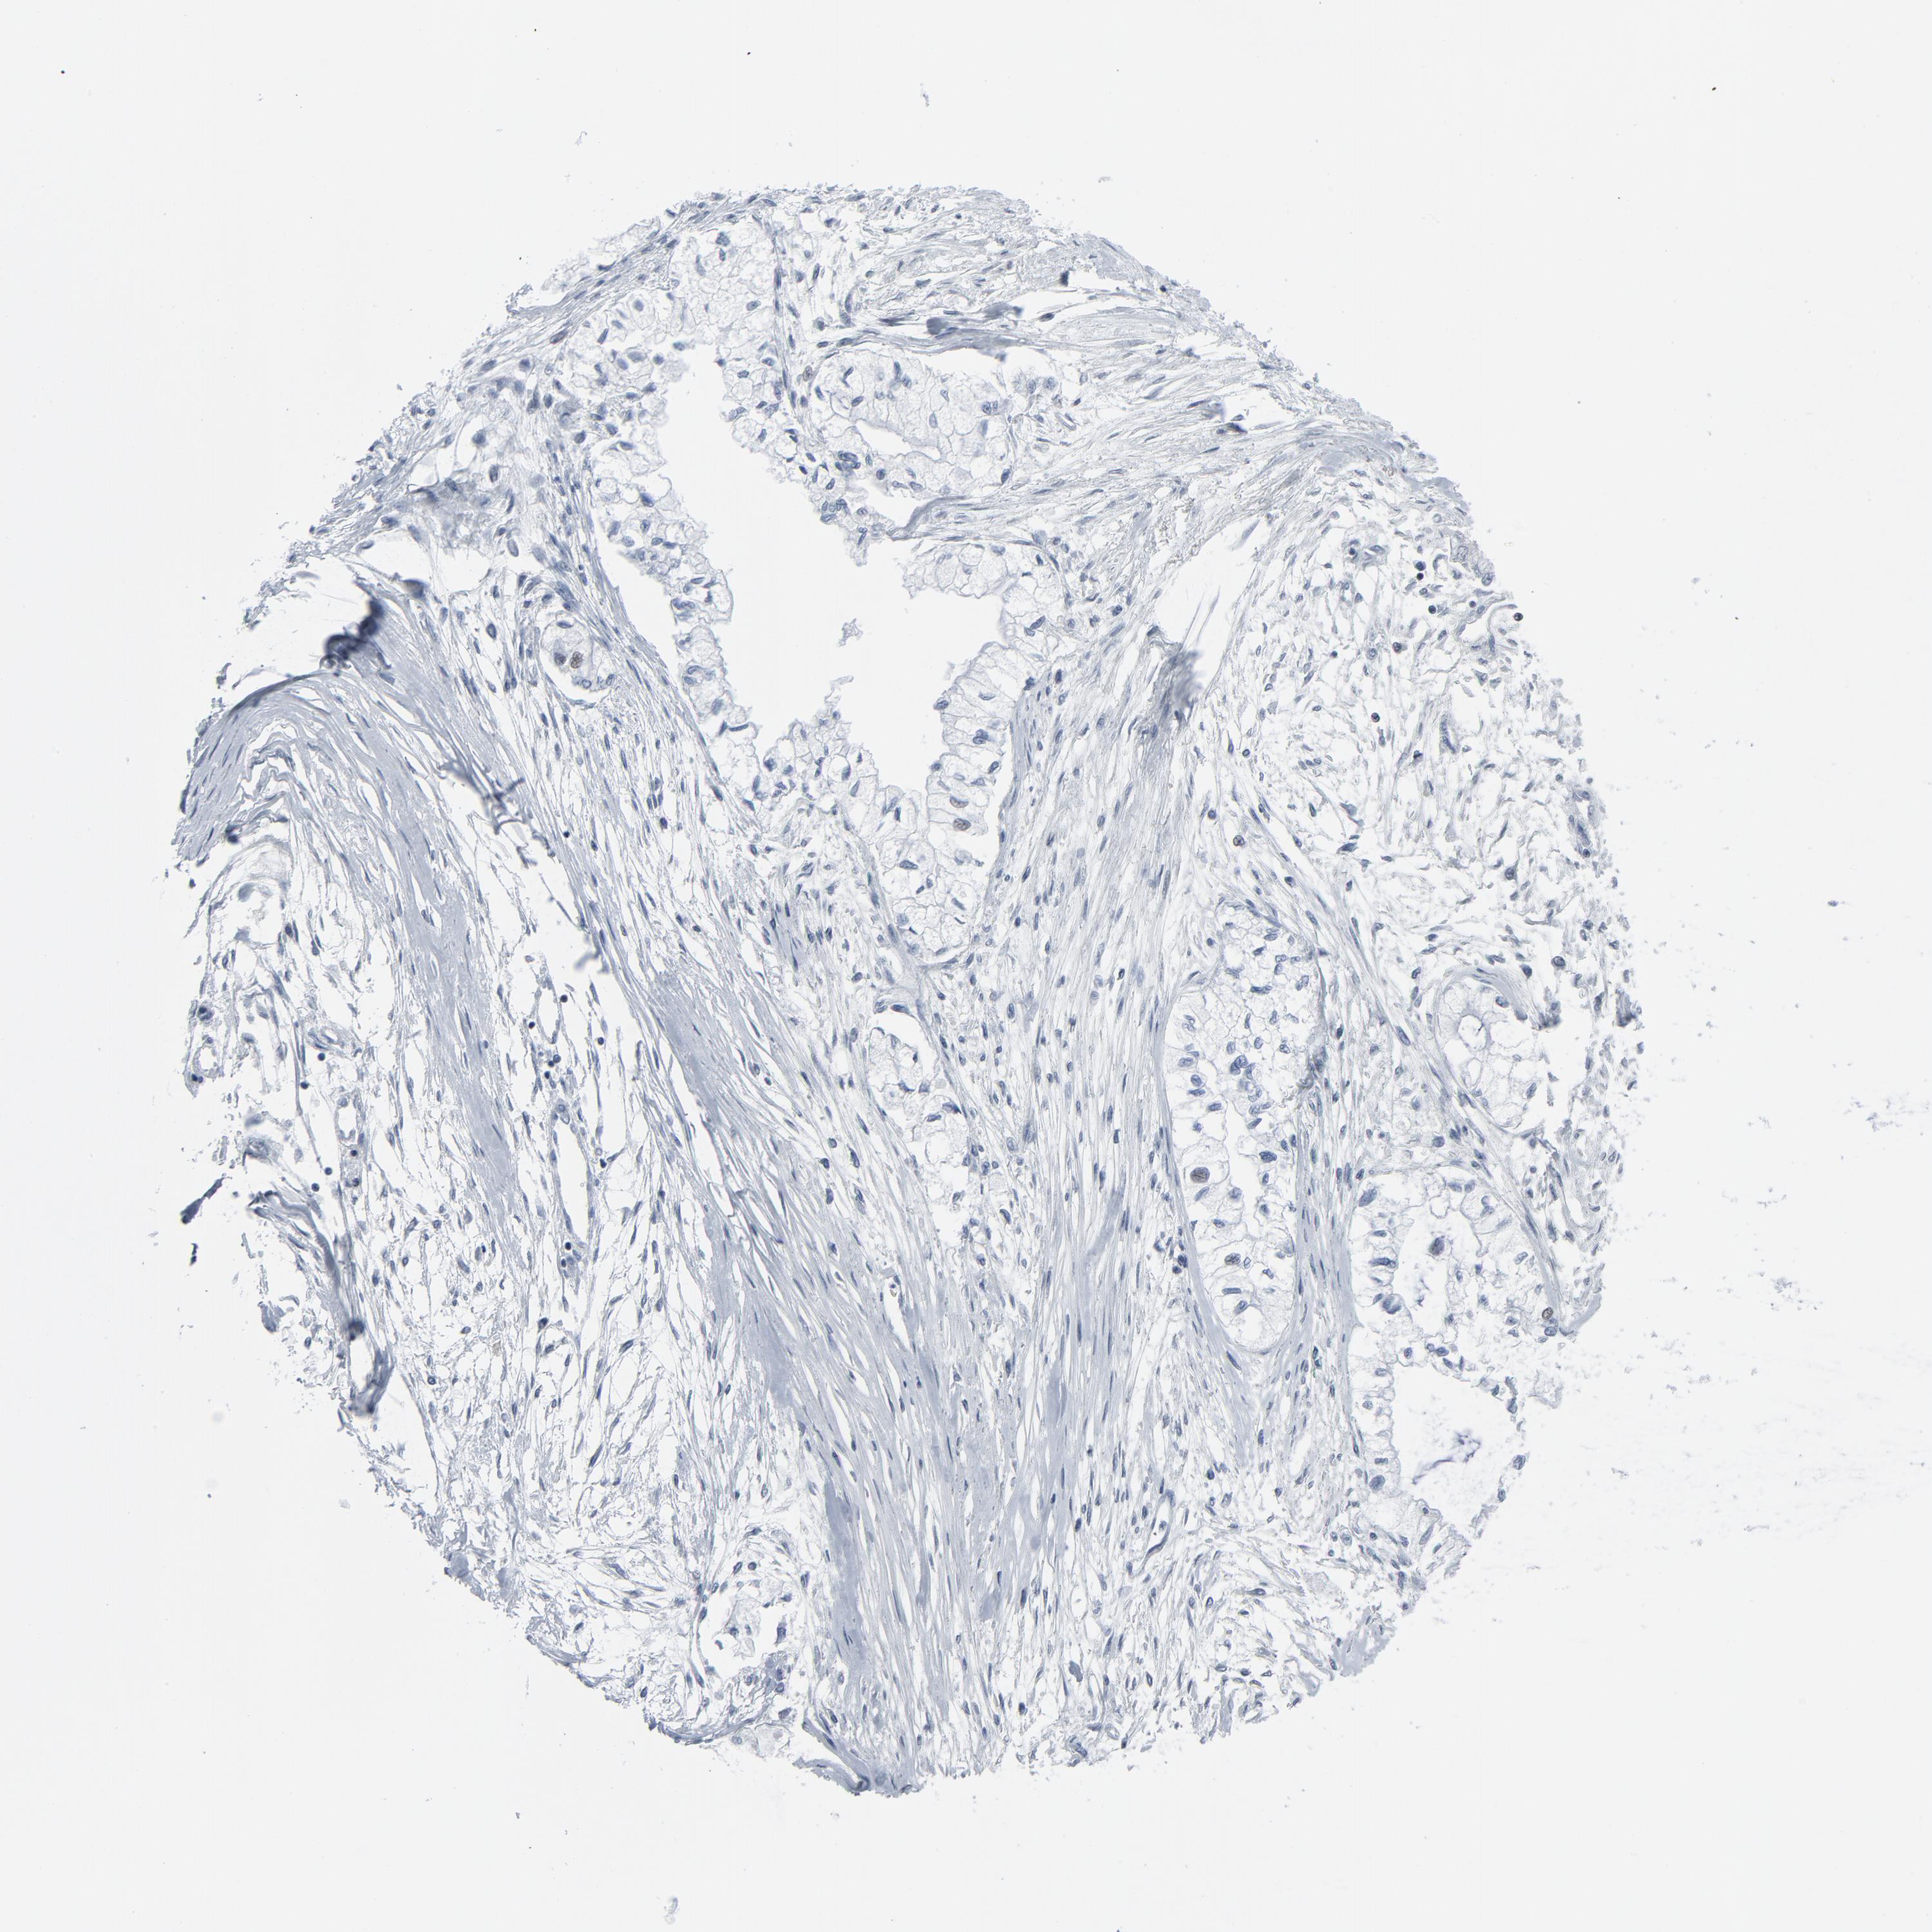

PANCREATIC CANCER - Protein expressioni

A mouse-over function shows sample information and annotation data. Click on an image to view it in a full screen mode. Samples can be filtered based on level of antibody staining by selecting one or several of the following categories: high, medium, low and not detected. The assay and annotation is described here.

Note that samples used for immunohistochemistry by the Human Protein Atlas do not correspond to samples in the TCGA dataset.

Antibody stainingi

Antibody staining in the annotated cell types in the current human tissue is reported as not detected, low, medium, or high, based on conventional immunohistochemistry profiling in selected tissues. This score is based on the combination of the staining intensity and fraction of stained cells.

Each image is clickable and will lead to virtual microscopy that enables deeper exploration of all samples and also displays staining intensity scores, fraction scores and subcellular localization as well as patient and tissue information for each sample.

HPA027873

HPA042128

HPA049883

HPA051156

CAB003860